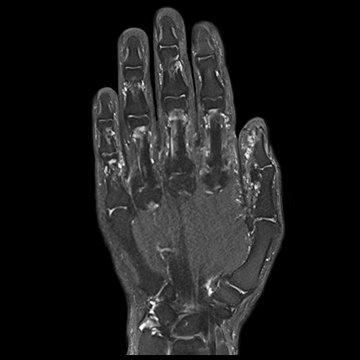

手・指関節

PD TSE,

PD TSE SPAIR,

T1 TSE